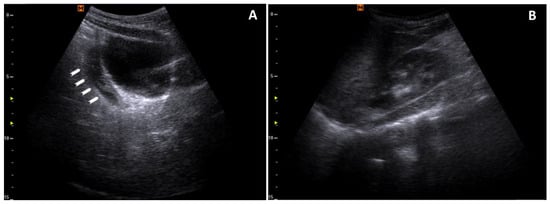

Upon admission to our PED, a complete POCUS was performed, which showed bilateral pleural effusion, mild pericardial effusion, and ascites without other signs of pulmonary parenchymal or cardiac involvement (Figure 1, Figure 2 and Figure 3). Bedside focused cardiac ultrasonography (FoCUS) allowed us to exclude systolic dysfunction or cardiac tamponade.

Figure 3. Peritoneal effusion: (A) a longitudinal scan of the bladder with retrovesical effusion (arrowheads); (B) the absence of effusion in the hepatorenal recess.